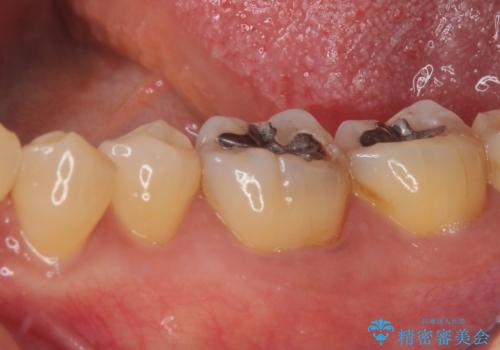

- 銀歯の周りに物が挟まるとのことで来院された患者様です。

咬合力が強く、銀歯周りの歯質に隙間が生じてむし歯になっている状態でした。

むし歯をしっかりと取り除き、強い咬合力を考慮してゴールドインレーにて修復することとしました。